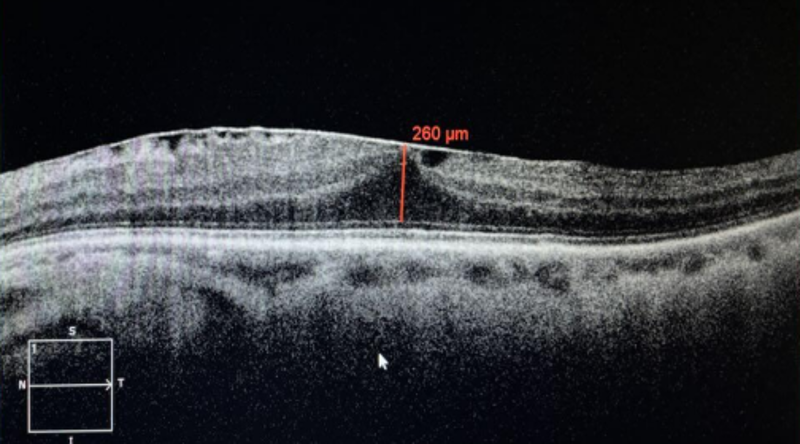

术后第一天,廖叔叔左眼视力从0.2提高到0.4,术后第一天复查OCT显示,那个曾经没被发现的黄斑前膜术后真的不见了,黄斑区的结构也立即恢复正常,廖叔叔带着满意的笑容办理了出院。

术后第一天左眼黄斑OCT:左眼黄斑区结构基本正常,未见明显前膜牵拉